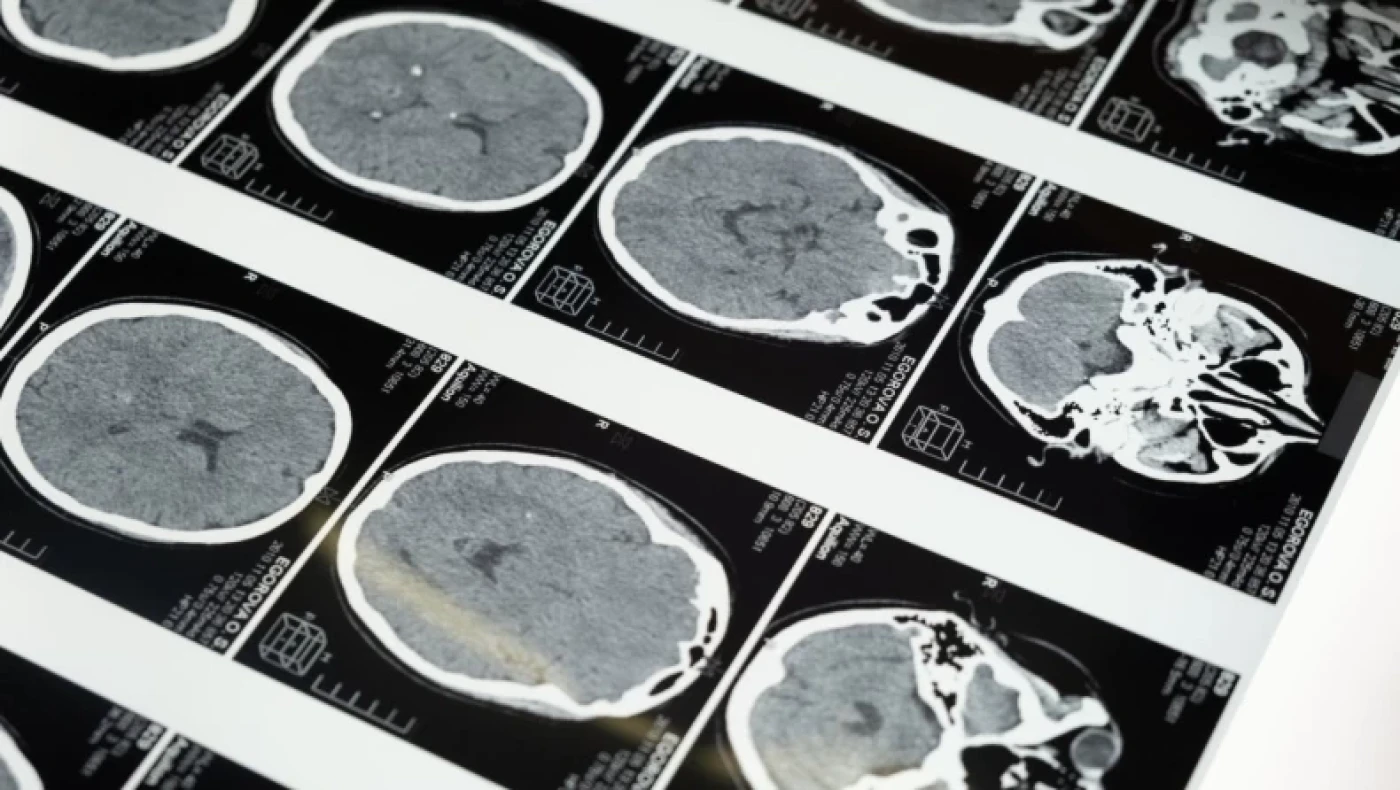

Μπορούσε να διαβάσει γράμματα και αριθμούς τυπωμένα ανάποδα και κανονικά, σαν να ήταν ακριβώς τα ίδια, και μπορούσε να διαβάσει την ώρα σε έναν δείκτη ρολογιού από οποιαδήποτε γωνία.

Έγινε αντικείμενο έντονης γοητείας για τον Ισπανό νευροεπιστήμονα Justo Gonzalo, ο οποίος τον μελέτησε επί 50 χρόνια.Η ανάλυση του Gonzalo οδήγησε τελικά σε μια σημαντική αλλαγή στον τρόπο με τον οποίο κατανοούμε τον εγκέφαλο, κυρίως χάρη στο συμπέρασμά του ότι ο εγκέφαλος δεν είναι απλώς μια συλλογή διακριτών τμημάτων αλλά ένα δυναμικό σύνολο.

Ο ασθενής Μ βοήθησε τον νευρολόγο να δει ότι οι επιπτώσεις της εγκεφαλικής βλάβης εξαρτώνται από το μέγεθος και τη θέση του τραύματος και ότι οι τραυματισμοί δεν καταστρέφουν συγκεκριμένες λειτουργίες, αλλά επηρεάζουν την ισορροπία μιας σειράς λειτουργιών.